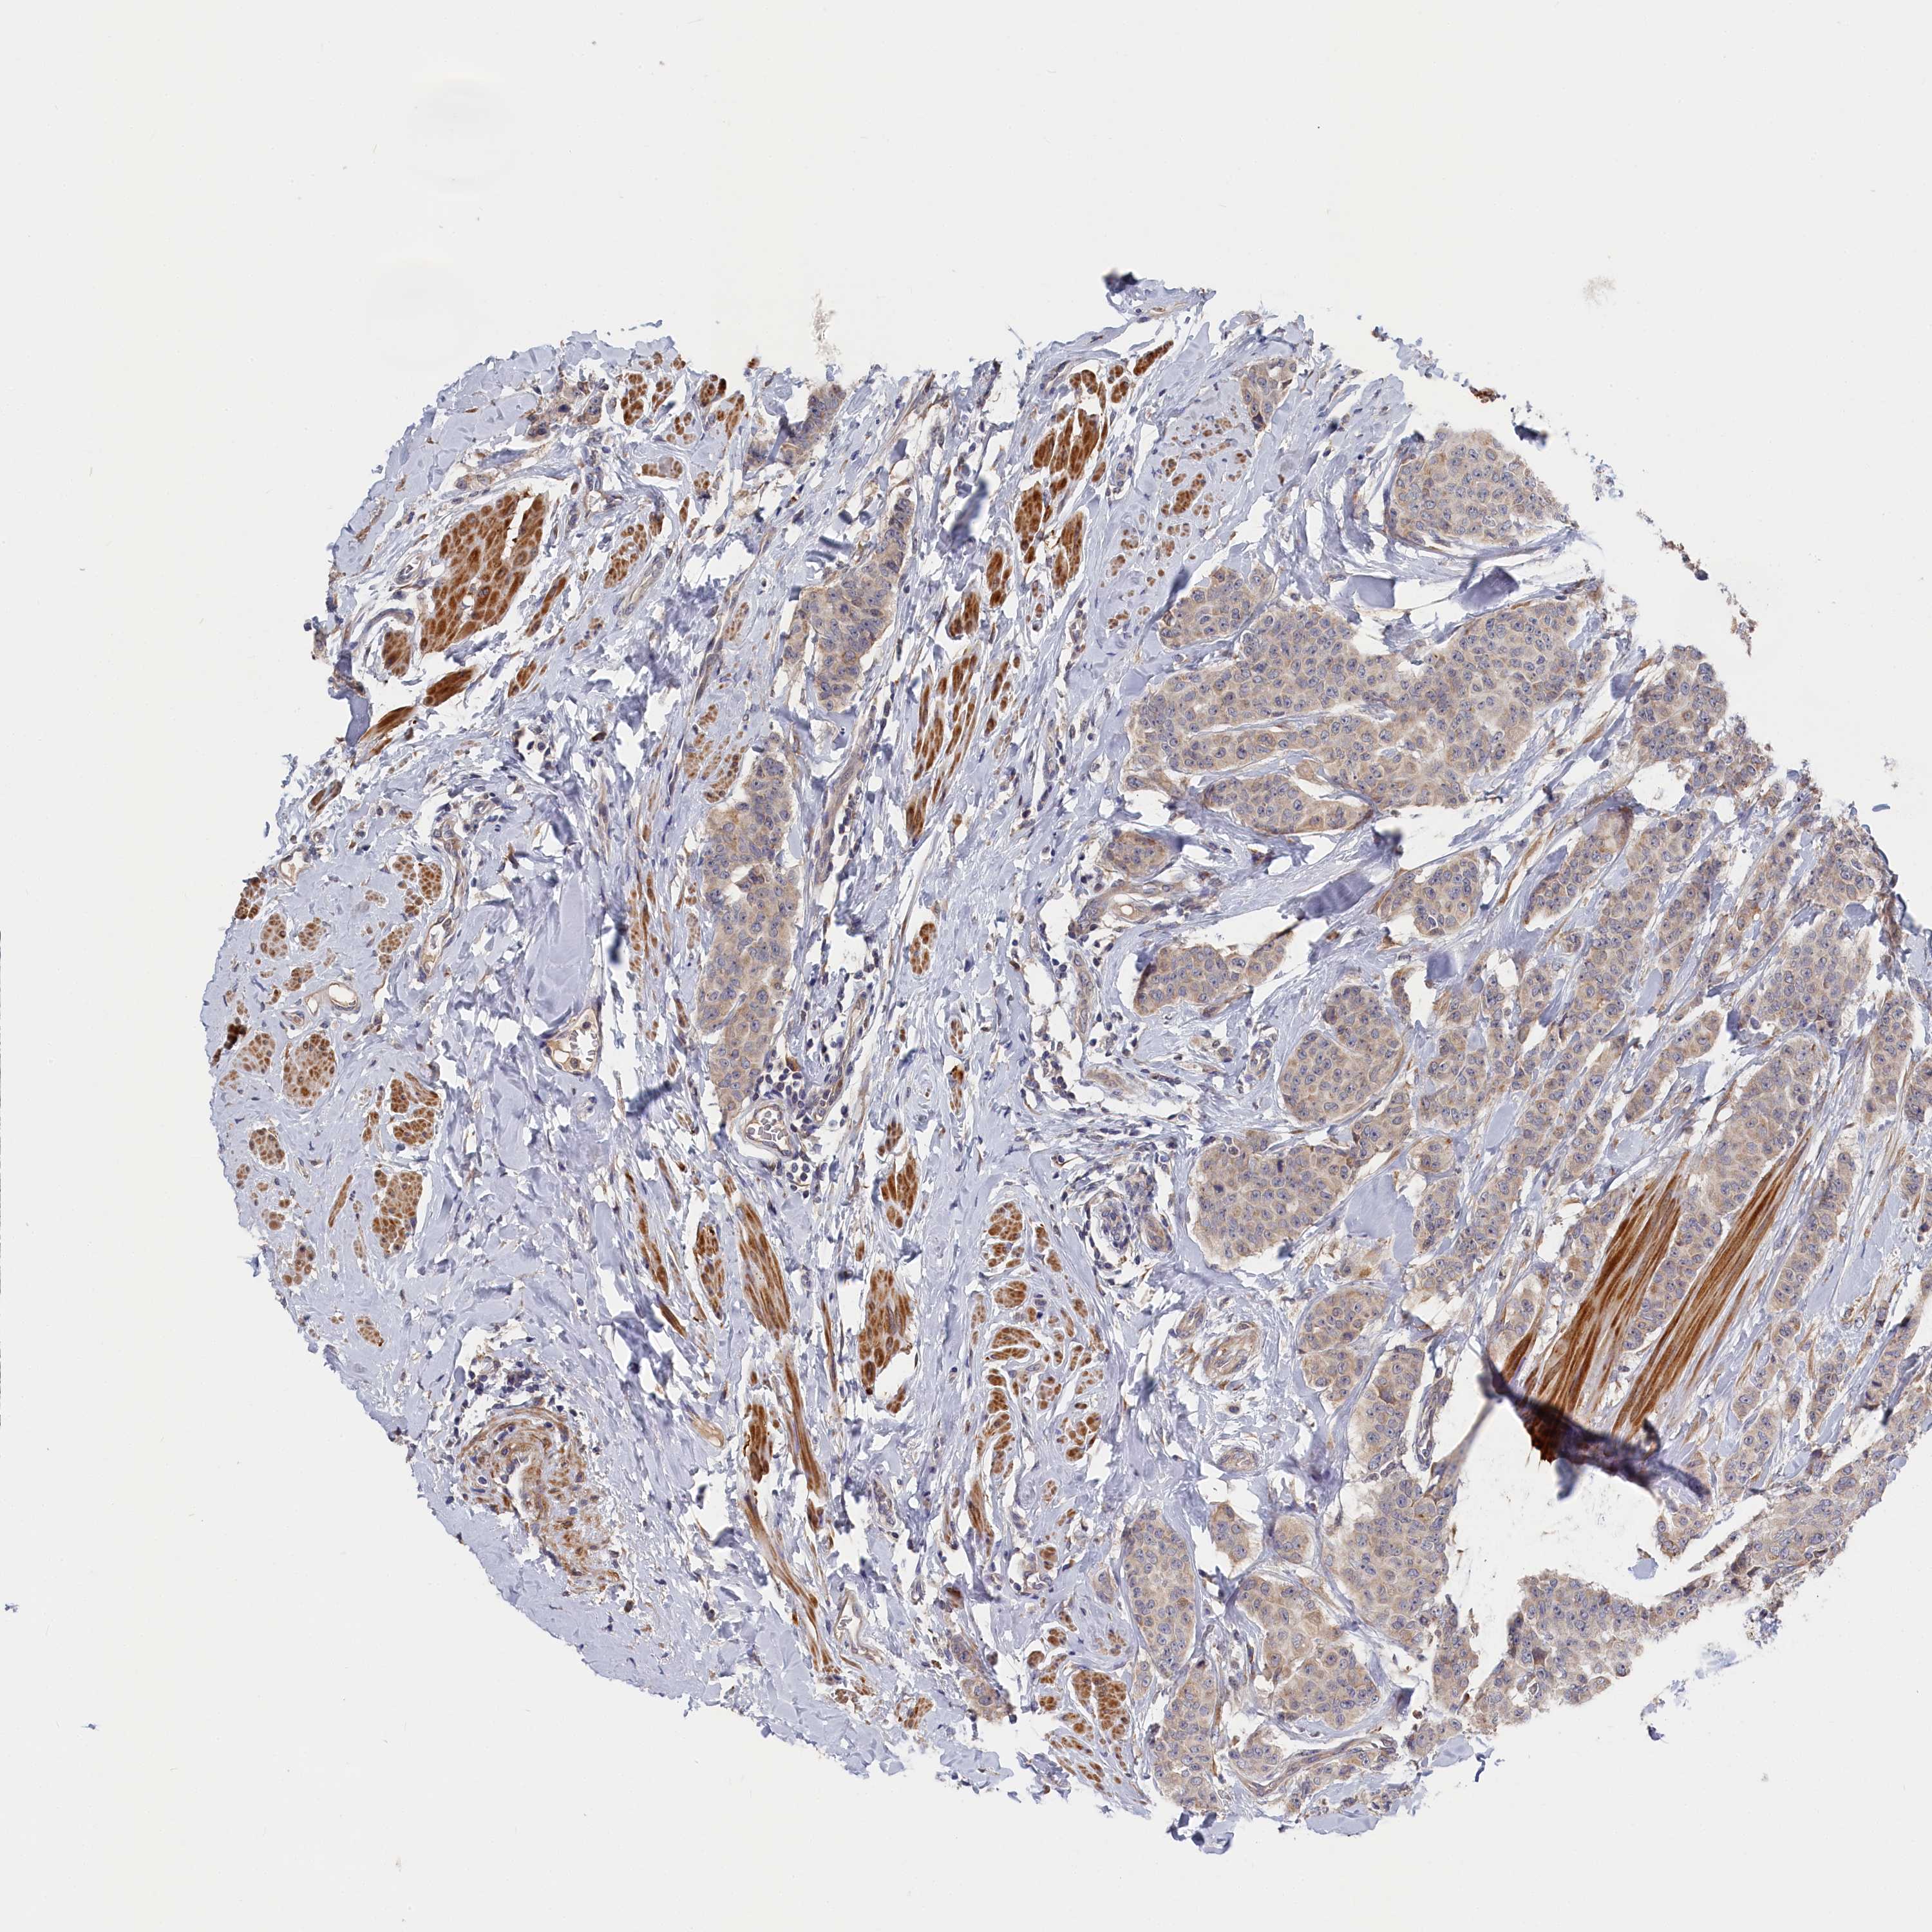

CANCER BREAST CANCER Show tissue menu

BRCA TCGA BRCA VALIDATION PROTEIN EXPRESSION